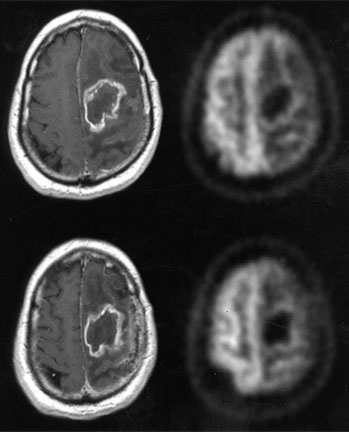

Exploración por PET mostrando un tumor cerebral

Nota: Las imágenes se muestra para fines ilustrativos. No trate de sacar conclusiones comparando esta imagen con otras en el sitio. Solamente los radiólogos calificados deben interpretar las imágenes.